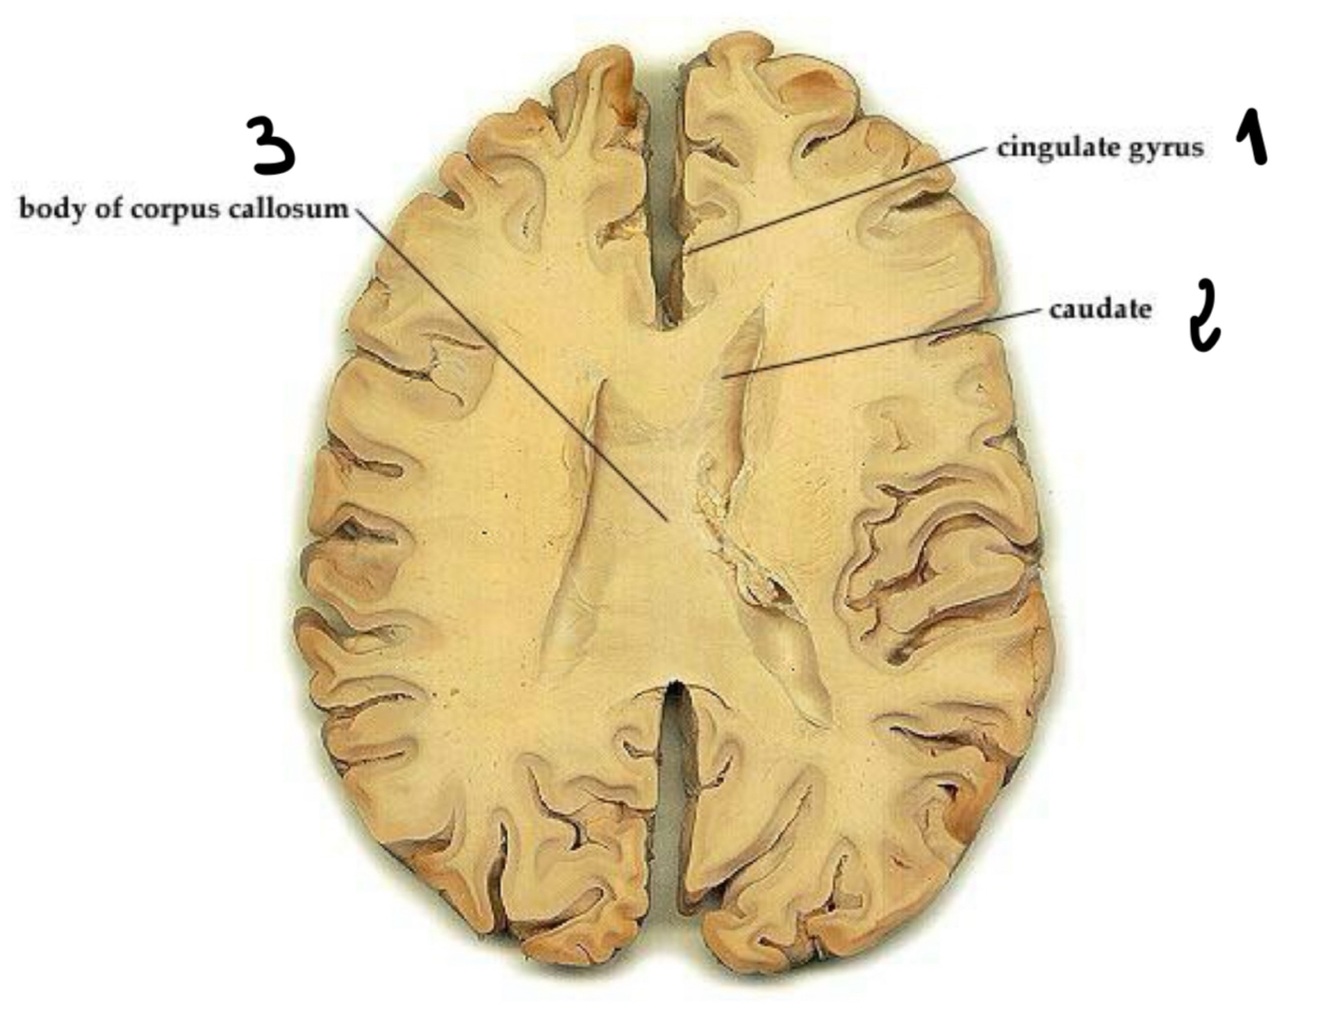

Patients with memory problems might have a malformation in … gyrus

CINGULATE